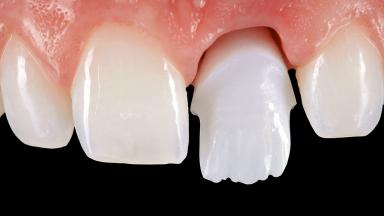

Open-Flap Debridement for the Management of Peri-Implant Mucositis Associated with Excess Cement

A 79-year-old female patient was referred to the Department of Periodontology of the University of Bern, Switzerland by her private dentist in May 2019. She had been rehabilitated in May 2005 with two tissue-level implants (Institut Straumann AG, Basel Switzerland) at sites 13 and 15, supporting a three-unit cemented fixed dental prosthesis (FDP). The metal-ceramic FDP had been cemented permanently with a glass-ionomer cement (Ketac Cem; 3M ESPE, Seefeld, Germany). Implant 13 had been diagnosed with peri-implant mucositis by the referring dentist in the course of regular supportive therapy. The patient was in good general health, did not smoke, and exhibited good self-performed plaque control.